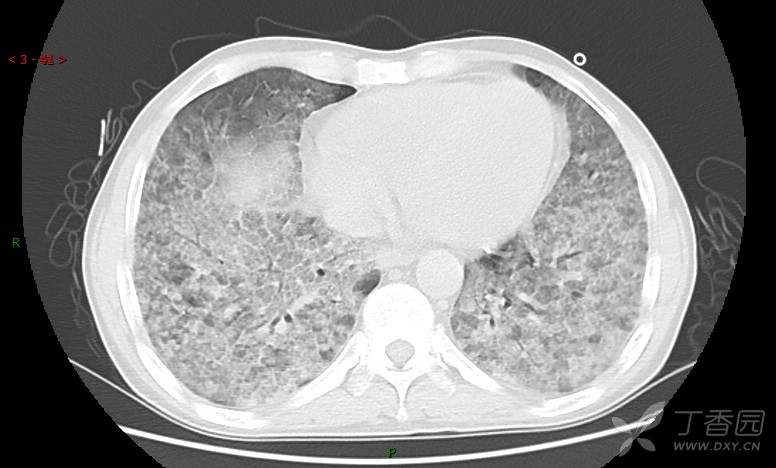

地图+铺路石征=PAP?那升高的CEA怎么说(病例3连发,附其他2例链接)

患者男,42岁,咳嗽半年余,加重伴憋喘2月余。

患者半年余前无明显诱因出现间断咳嗽,干咳为主,偶咳少量黄白痰,剧烈咳嗽或运动后可出现轻度憋喘,无高热、脓臭痰,无胸痛、咯血及晕厥,无低热乏力及盗汗,无心前区压榨感及夜间阵发性呼吸困难,初未在意,未予正规诊治。2月余前患者自觉上述症状较前加重,咳嗽、憋喘明显,黄白色粘痰略有增多,伴有发热,热前伴有畏寒、寒战,体温最高达38.9℃,先后就诊多家医院,入住重症监护室,未行气管插管,考虑“重症肺炎”,给予“美罗培南、复方磺胺甲噁唑”等药物抗感染,“卡泊芬净”抗真菌,并给予“甲泼尼龙”等药物治疗35天,经治疗后症状好转于2018-04-02出院。患者自出院后仅应用中药治疗(具体不详),并给予家庭氧疗,平素仍有间断咳嗽,咳少量黄白色粘痰,活动后憋喘明显,活动耐量差,以卧床为主。

血清肿瘤相关抗原116.22U/ml↑(0--95);

癌胚抗原 61.96 ng/mL ↑ 0--5

神经特异性烯醇化酶 33.12 ng/ml ↑ 0--16.3

细胞角蛋白19片段测定 40.23 ng/ml ↑ ≤3.3

肺内弥漫性网状结节影,PET-CT却无阳性病灶,这是?(附其他2例链接)